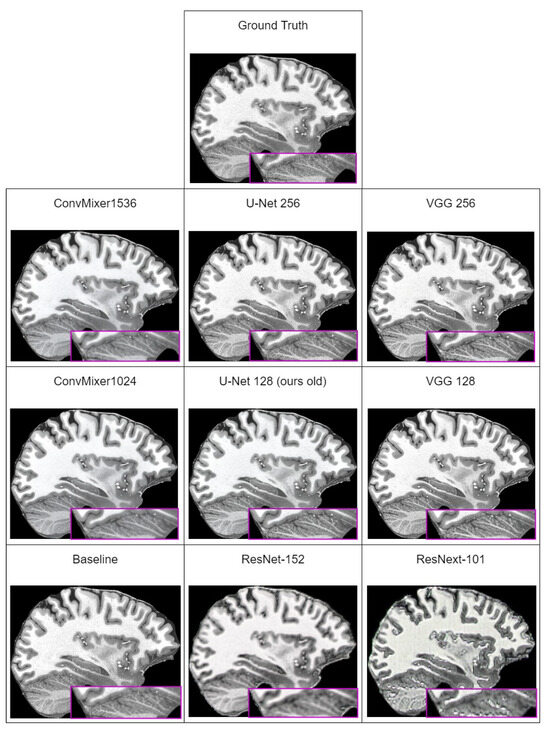

In Table 6, we can see that the best perceptual quality results are achieved with the ConvMixer1536 model used as discriminator. However, looking at the subjective comparison in Figure 4, it seems that the LPIPS metric does not capture artifacts that are present in images generated by ConvMixer models. Comparing subjectively generated images, images generated using U-Net or VGG are far more close to ground-truth images. This means that LPIPS is unable to correctly quantify perceptual quality of generated images. Similar remarks were made by other researchers, for example, those in [78] (which investigated why artifacts appear and how to reduce them) that all currently used perceptual quality metrics are unable to capture existence of these artifacts in the generated images as a decrease in the metric score.

Excluding the fact that LPIPS does not capture artifacts, and therefore, results with ConvMixers are not subjectively best, new methodology improvements increased all of the metric values over the last iteration. The best overall result is achieved with the U-Net discriminator, which uses 256 input features.